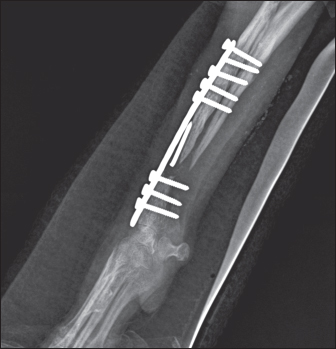

То harvest the autogenous cortical graft, a caudal approach to the contralateral ulnar diaphysis was used (Fig. 2). The subcutaneous tissue was bluntly dissected, and thereafter retraction was maintained using Gelpi retractors. A Hohmann retractor was placed between the ulna and radius to prevent iatrogenic damage to the radius. A 4.8 cm long bone segment of the ulnar diaphysis was removed by means of an oscillating saw. The ostectomy and periosteum were removed en bloc and transferred into the surgical gap of the right radius. At both ends of the cortical autograft, a cancellous graft soaked with 1,000 IU recombinant human erythropoietin (Binocrit®, 2000 IU, Sandoz GmbH, Kundl, Austria) was applied for optimization of osteoinduction and angiogenesis. To collect the cancellous graft, a small incision was made over the craniolateral aspect of the greater trochanter. A 3.5-mm hole in the proximal humeral metaphysis was created with a drill bit and a bone curette was used to harvest the cancellous graft. Then, it was inserted into the recipient site as soon as possible to minimize cell death. After proper alignment of bone fragments, they were fixed with a dynamic compression plate (1.5 mm thickness) and 8 cortical screws: 2 in the distal radial fragment, 3 in the cortical graft, and 3 in the proximal radial fragment (Fig. 3). The intradermal layer was closed with an absorbable monofilament suture material (PDX, 3-0, VetSuture, France), followed by non-absorbable skin sutures (Nylon, 3-0, Kruuse, Denmark).

Fig. 2. Collection of bone autograft after caudal approach to the contralateral ulnar dyaphysis (left) and placement of the bone graft in the radial defect (right).